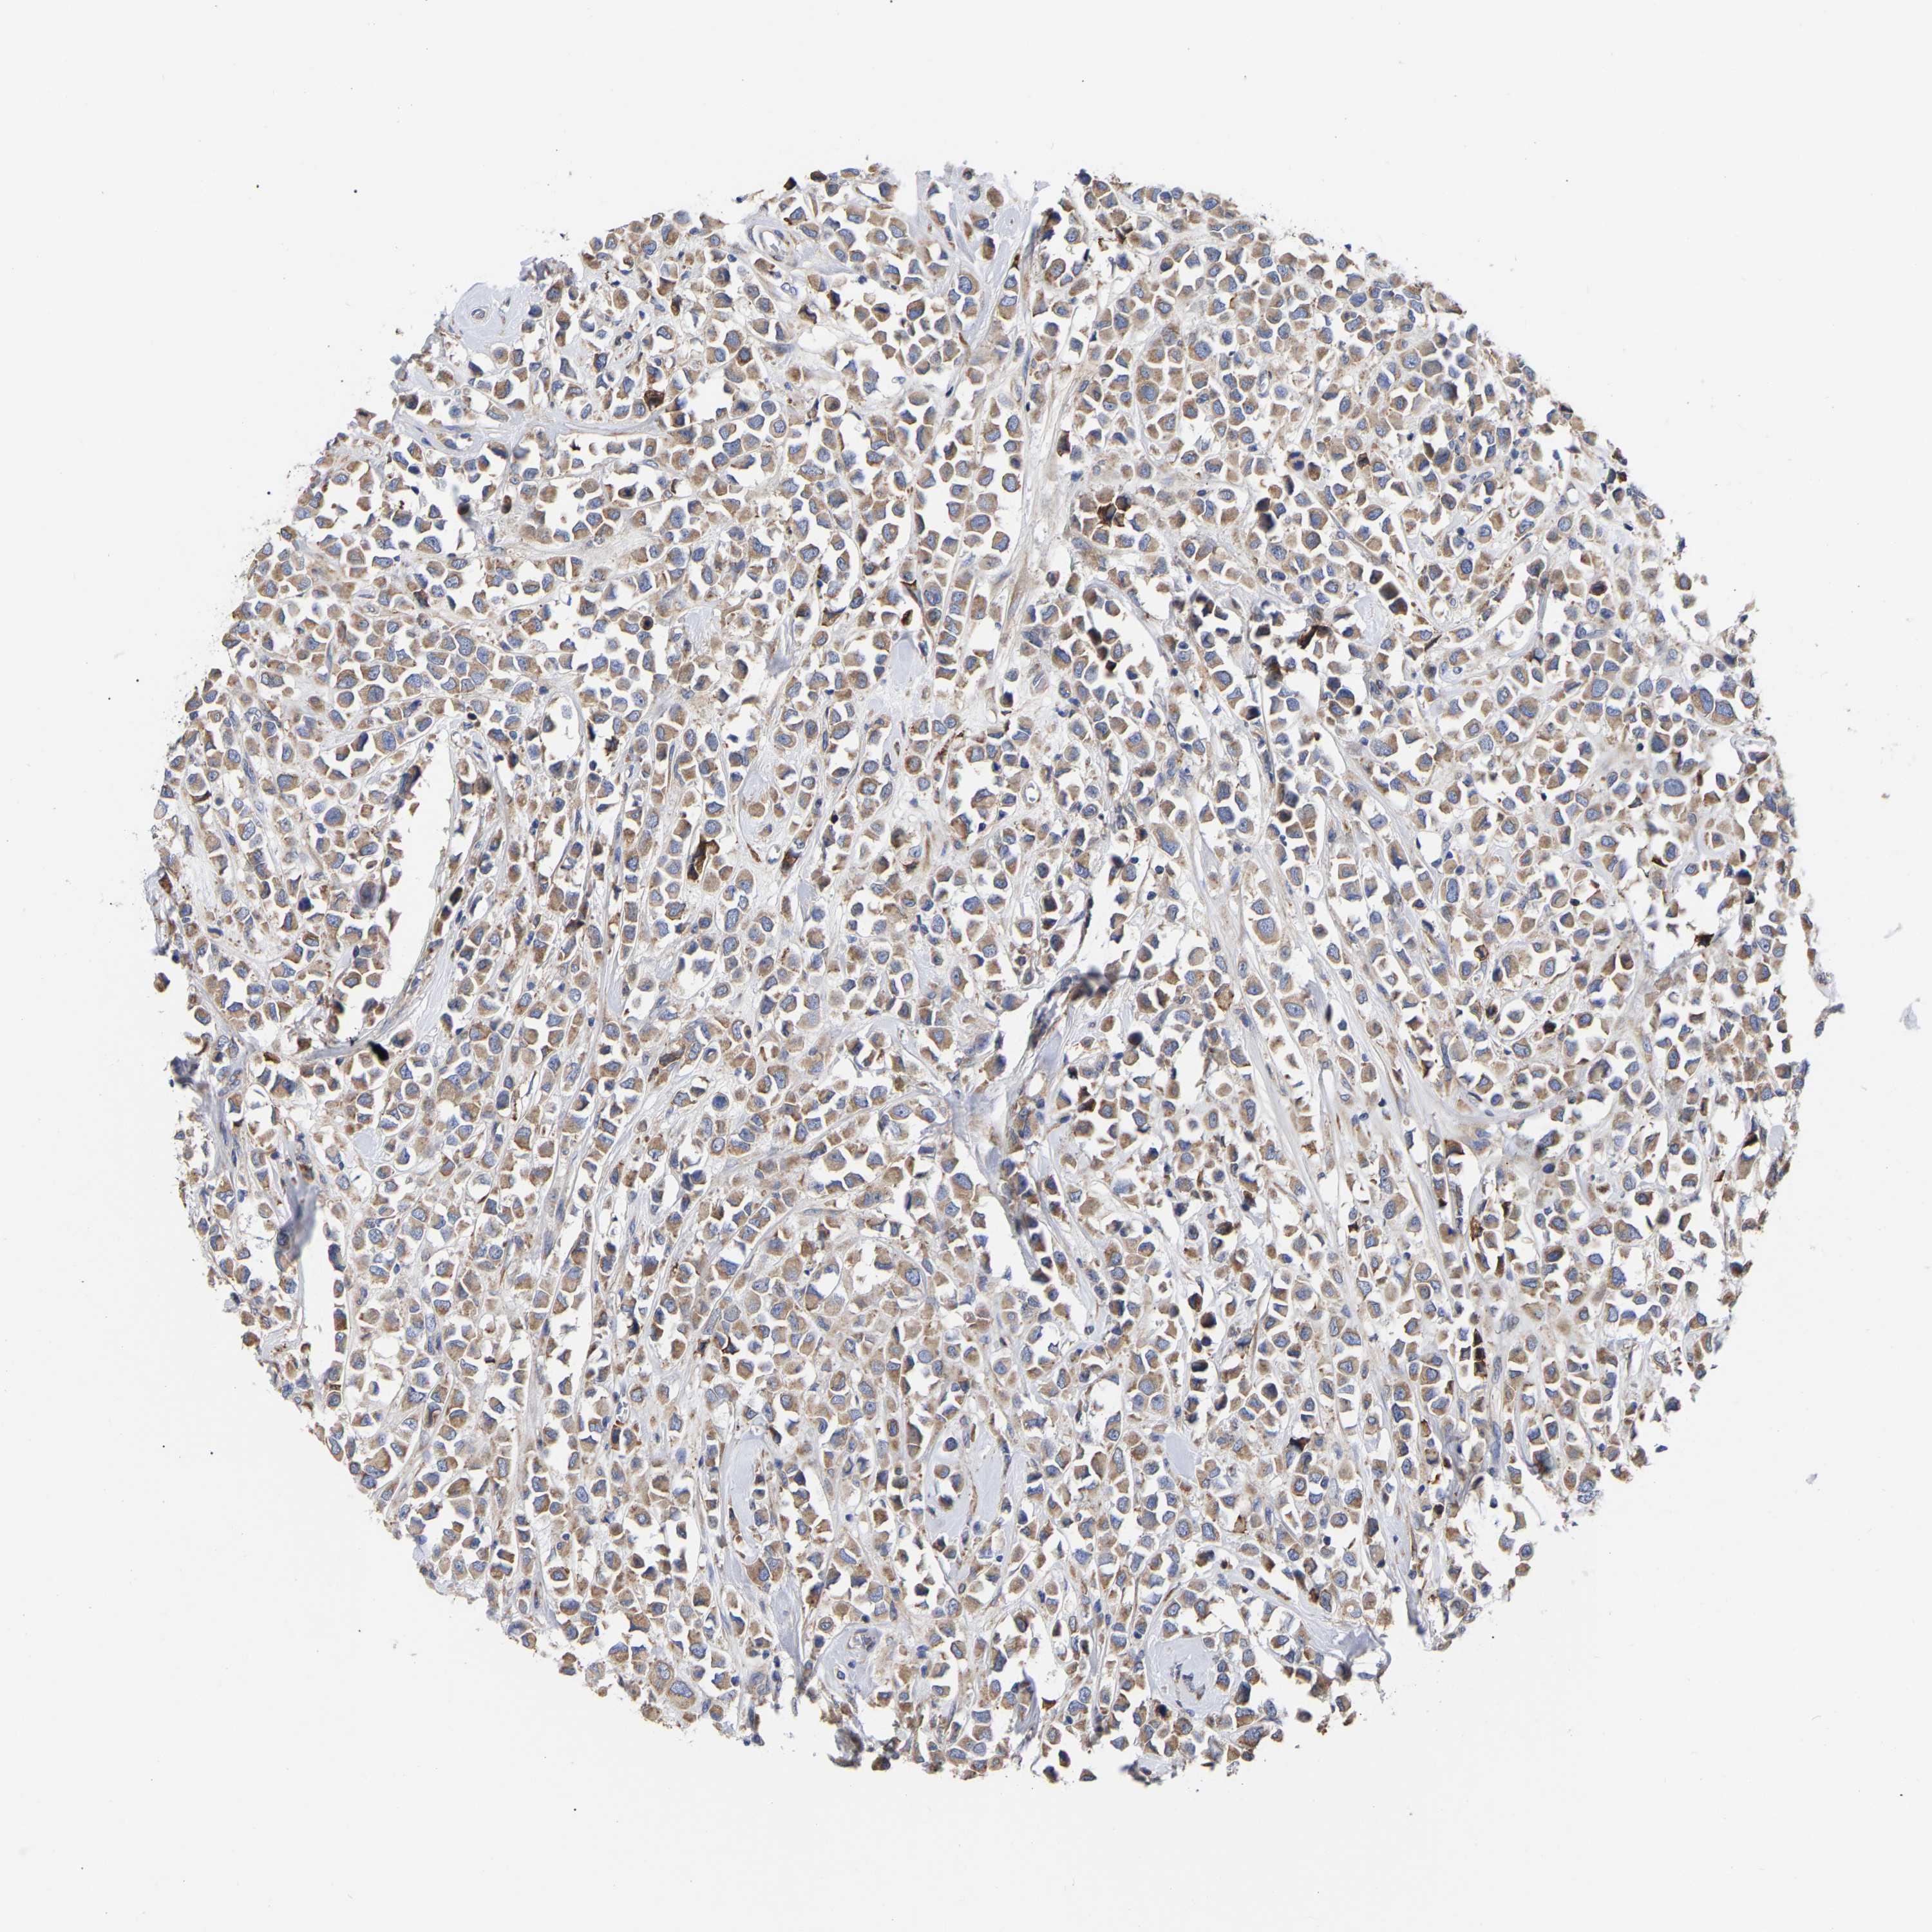

CANCER BREAST CANCER Show tissue menu

BRCA TCGA BRCA VALIDATION PROTEIN EXPRESSION